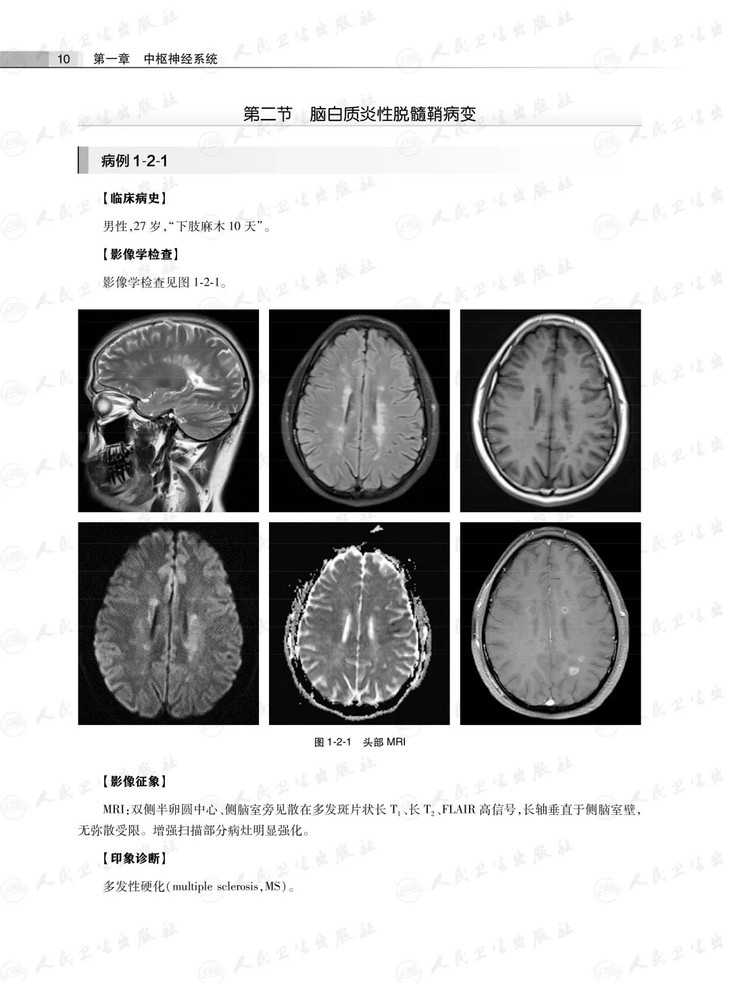

第二节脑白质炎性脱髓鞘病变